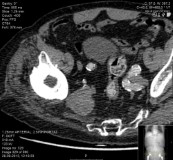

At this stage the neurological lesion was considered a complication of the arthroplastic procedure. Electromyography was performed and revealed a high injury of peroneal part of the sciatic nerve. The CT study showed a mass exerting compressive effect in the sciatic notch, which at first sight would be interpreted as surgical material.

Due to vascular background, it was requested observation by a vascular surgeon. Clinical evaluation in combination with a family history of serious vascular disease (several family members amputated) put the possibility that the identified mass was of vascular origin.

CT angiography (Figure 3) of the lower limb confirmed the aneurysmal origin of the sciatic nerve compression lesion with origin on the right internal iliac artery. It was completely occluded with a thrombosed aneurysm with approximately 4x5cm.

Figure 4 Iliac aneurysm.

Figure 5 Right iliac aneurysm.

Figure 6 Sacral roots.